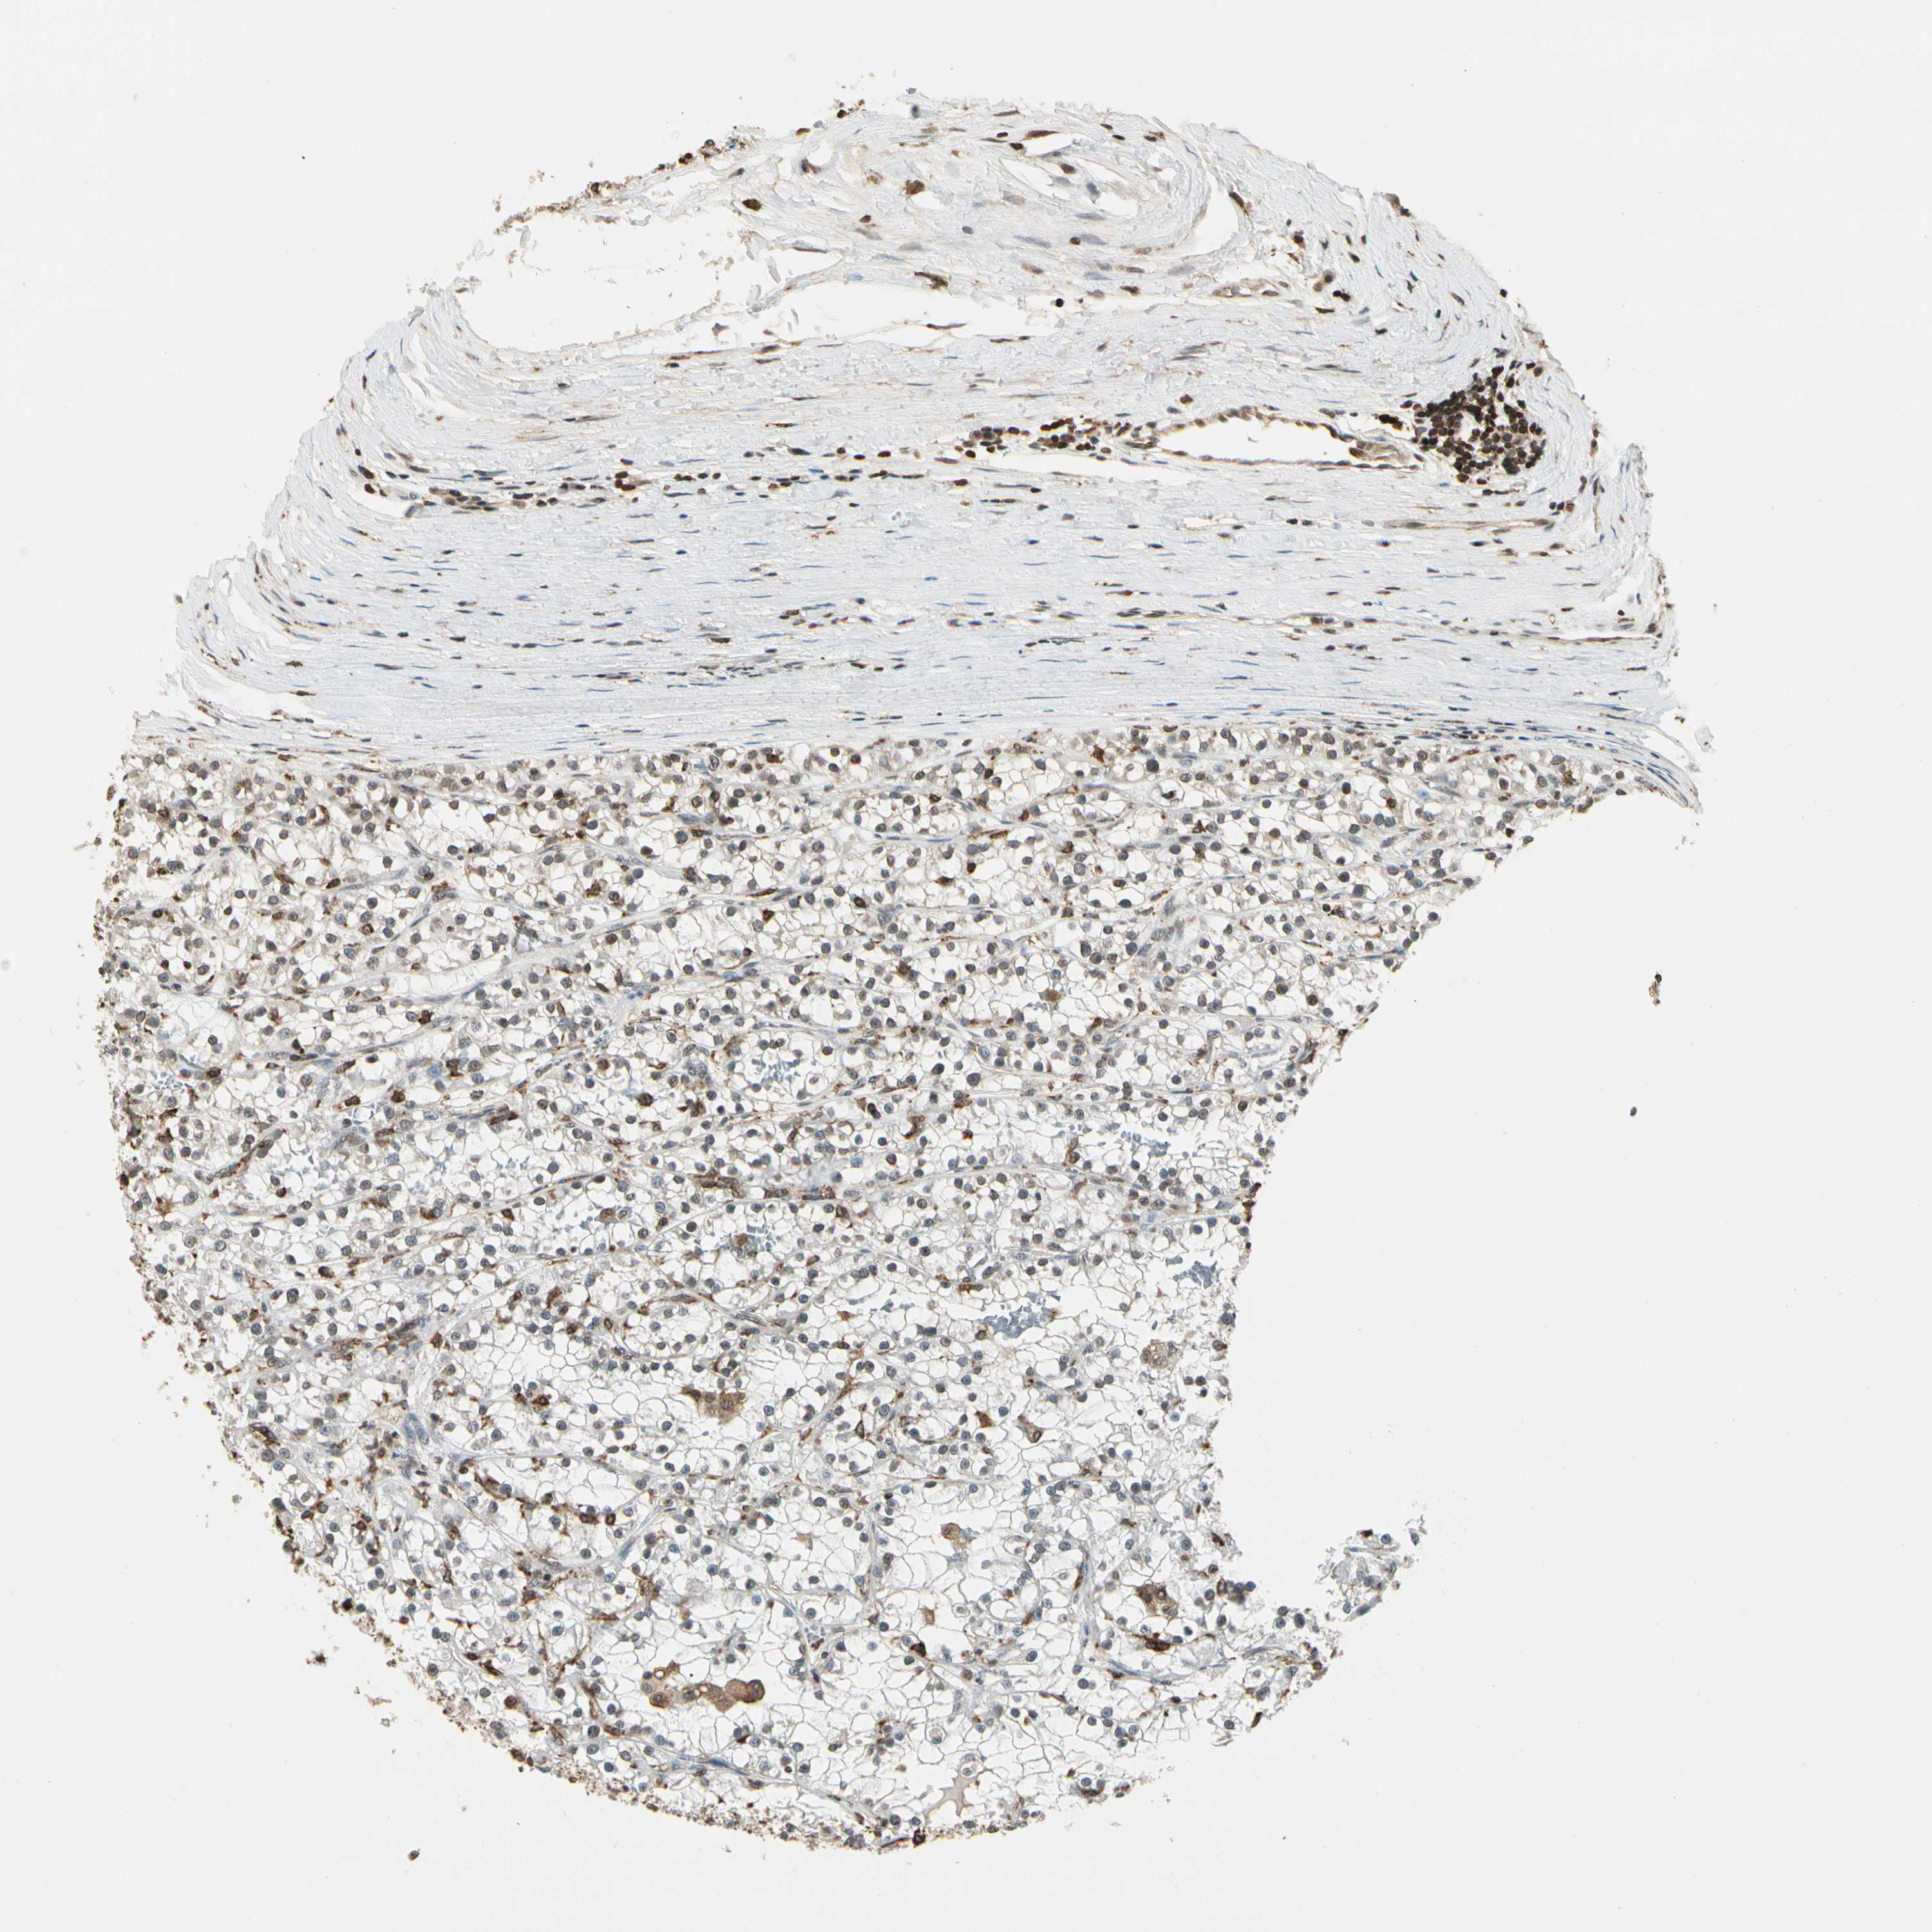

KIDNEY RENAL CLEAR CELL CARCINOMA (VALIDATION) - Interactive survival scatter ploti

The Survival Scatter plot shows the clinical status (i.e. dead or alive) for all individuals in the patient cohort, based on the same data that underlies the corresponding Kaplan-Meier plots. Patients that are alive at last time for follow-up are shown in blue and patients who have died during the study are shown in red.

The x-axis shows the expression levels (FPKM) of the investigated gene in the tumor tissue at the time of diagnosis. The y-axis shows the follow-up time after diagnosis (years). Both axes are complimented with kernel density curves demonstrating the data density over the axes. The top density plot shows the expression levels (FPKM) distribution among dead (red) and alive patients (blue). The right density plot shows the data density of the survived years of dead patients with high and low expression levels respectively, stratified using the cutoff indicated by the vertical dashed line through the Survival Scatter plot. This cutoff is automatically defined based on the FPKM cutoff that minimizes the p-score. The cutoff can be changed by dragging the vertical line or by entering a cutoff value in the square labeled "Current cut-off".

Under the Survival Scatter plot the p-score landscape (black curve; left axis) is shown together with dead median separation (red curve; right axis). Dead median separation is the difference in median mRNA expression between patients who have died with high and low expression, respectively. It is calculated as follows: median FPKM expression of dead patients with high expression - median FPKM expression of dead patients with low expression. This is intended to aid the user in visually exploring custom cutoffs and the associated p-scores and dead median separation.

Individual patient data is displayed and can be filtered by clicking on one or more of the category buttons on the top of the page. Categories describing expression level and patient information include: high, low, alive, dead, female, male and tumor stages. The scale of the x-axis can be toggled between linear and log-scale by clicking on the "x log" button. Mouse-over function shows TCGA ID, patient information and mRNA expression (FPKM) for each patient.

& Survival analysisi

Kaplan-Meier plots summarize results from analysis of correlation between mRNA expression level and patient survival. Patients were divided based on level of expression into one of the two groups "low" (under cut off) or "high" (over cut off). X-axis shows time for survival (years) and y-axis shows the probability of survival, where 1.0 corresponds to 100 percent.

FER is not prognostic in Kidney Renal Clear Cell Carcinoma (validation)

Best expression cut offi

: 4.58

P scorei

N/A

Average pTPM 4.6

Number of samples 100